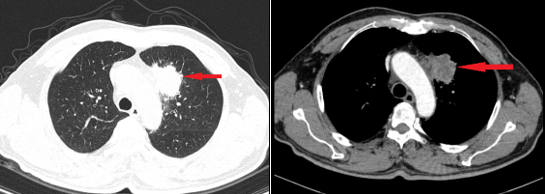

ทีมแพทย์จากศูนย์เวชศาสตร์นิวเคลียร์และมะเร็งวิทยา โรงพยาบาลบั๊กไม ได้วินิจฉัยว่าผู้ป่วยมีเนื้องอกในปอด (กลีบบนของปอดซ้าย) ซึ่งผลการตรวจชิ้นเนื้อยืนยันว่าเป็น มะเร็งชนิดต่อม (Adenocarcinoma) ซึ่งเกิดที่ปอด

ระหว่างกระบวนการตรวจเพิ่มเติม แพทย์ได้ทำการส่องกล้องลำไส้ใหญ่ และพบแผลคล้ายแผลหลุมที่บริเวณลำไส้ใหญ่ พร้อมผลชิ้นเนื้อยืนยันว่าเป็น มะเร็งลำไส้ใหญ่

ผลการตรวจเพิ่มเติมอื่นๆ เช่น CT ช่องท้อง, MRI สมอง และอัลตราซาวด์ต่อมน้ำเหลือง ไม่พบการแพร่กระจายของมะเร็งไปยังอวัยวะอื่น